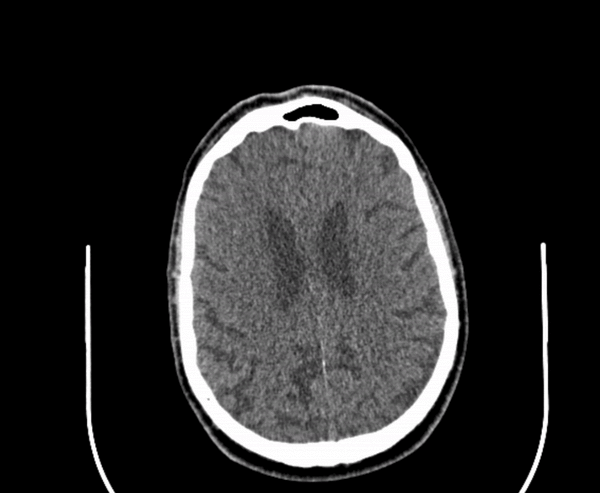

If a picture is worth 1000 words, how many words is a DICOM?

A tool for interactive case presentations